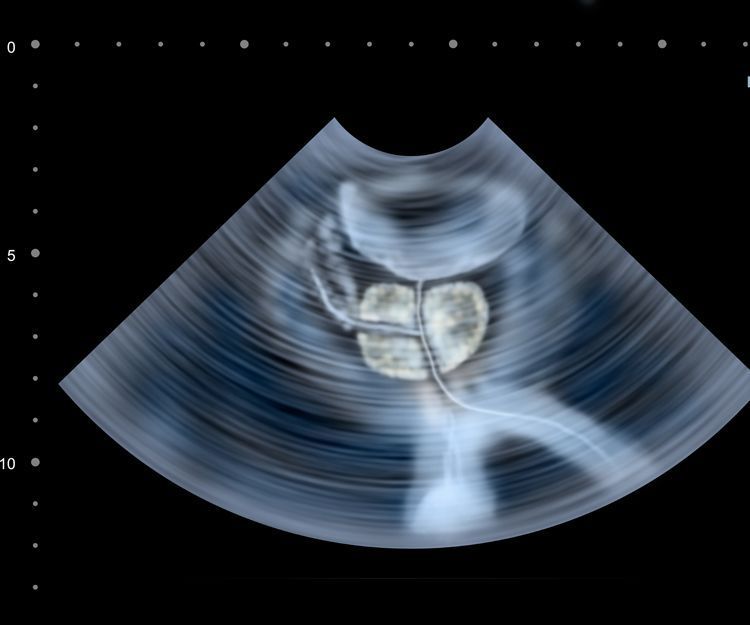

Pueden ser muchas y variadas las causas de sufrir problemas de impotencia y en Oviedo puedes acudir a la consulta del doctor Manuel Rivas del Fresno, Urólogo-Andrólogo para que realice un estudio y diagnóstico de tu caso concreto y establezca el tipo de tratamiento adecuado. Este tipo de problemas son disfunciones sexuales que pueden mermar la calidad de vida de muchos hombres.